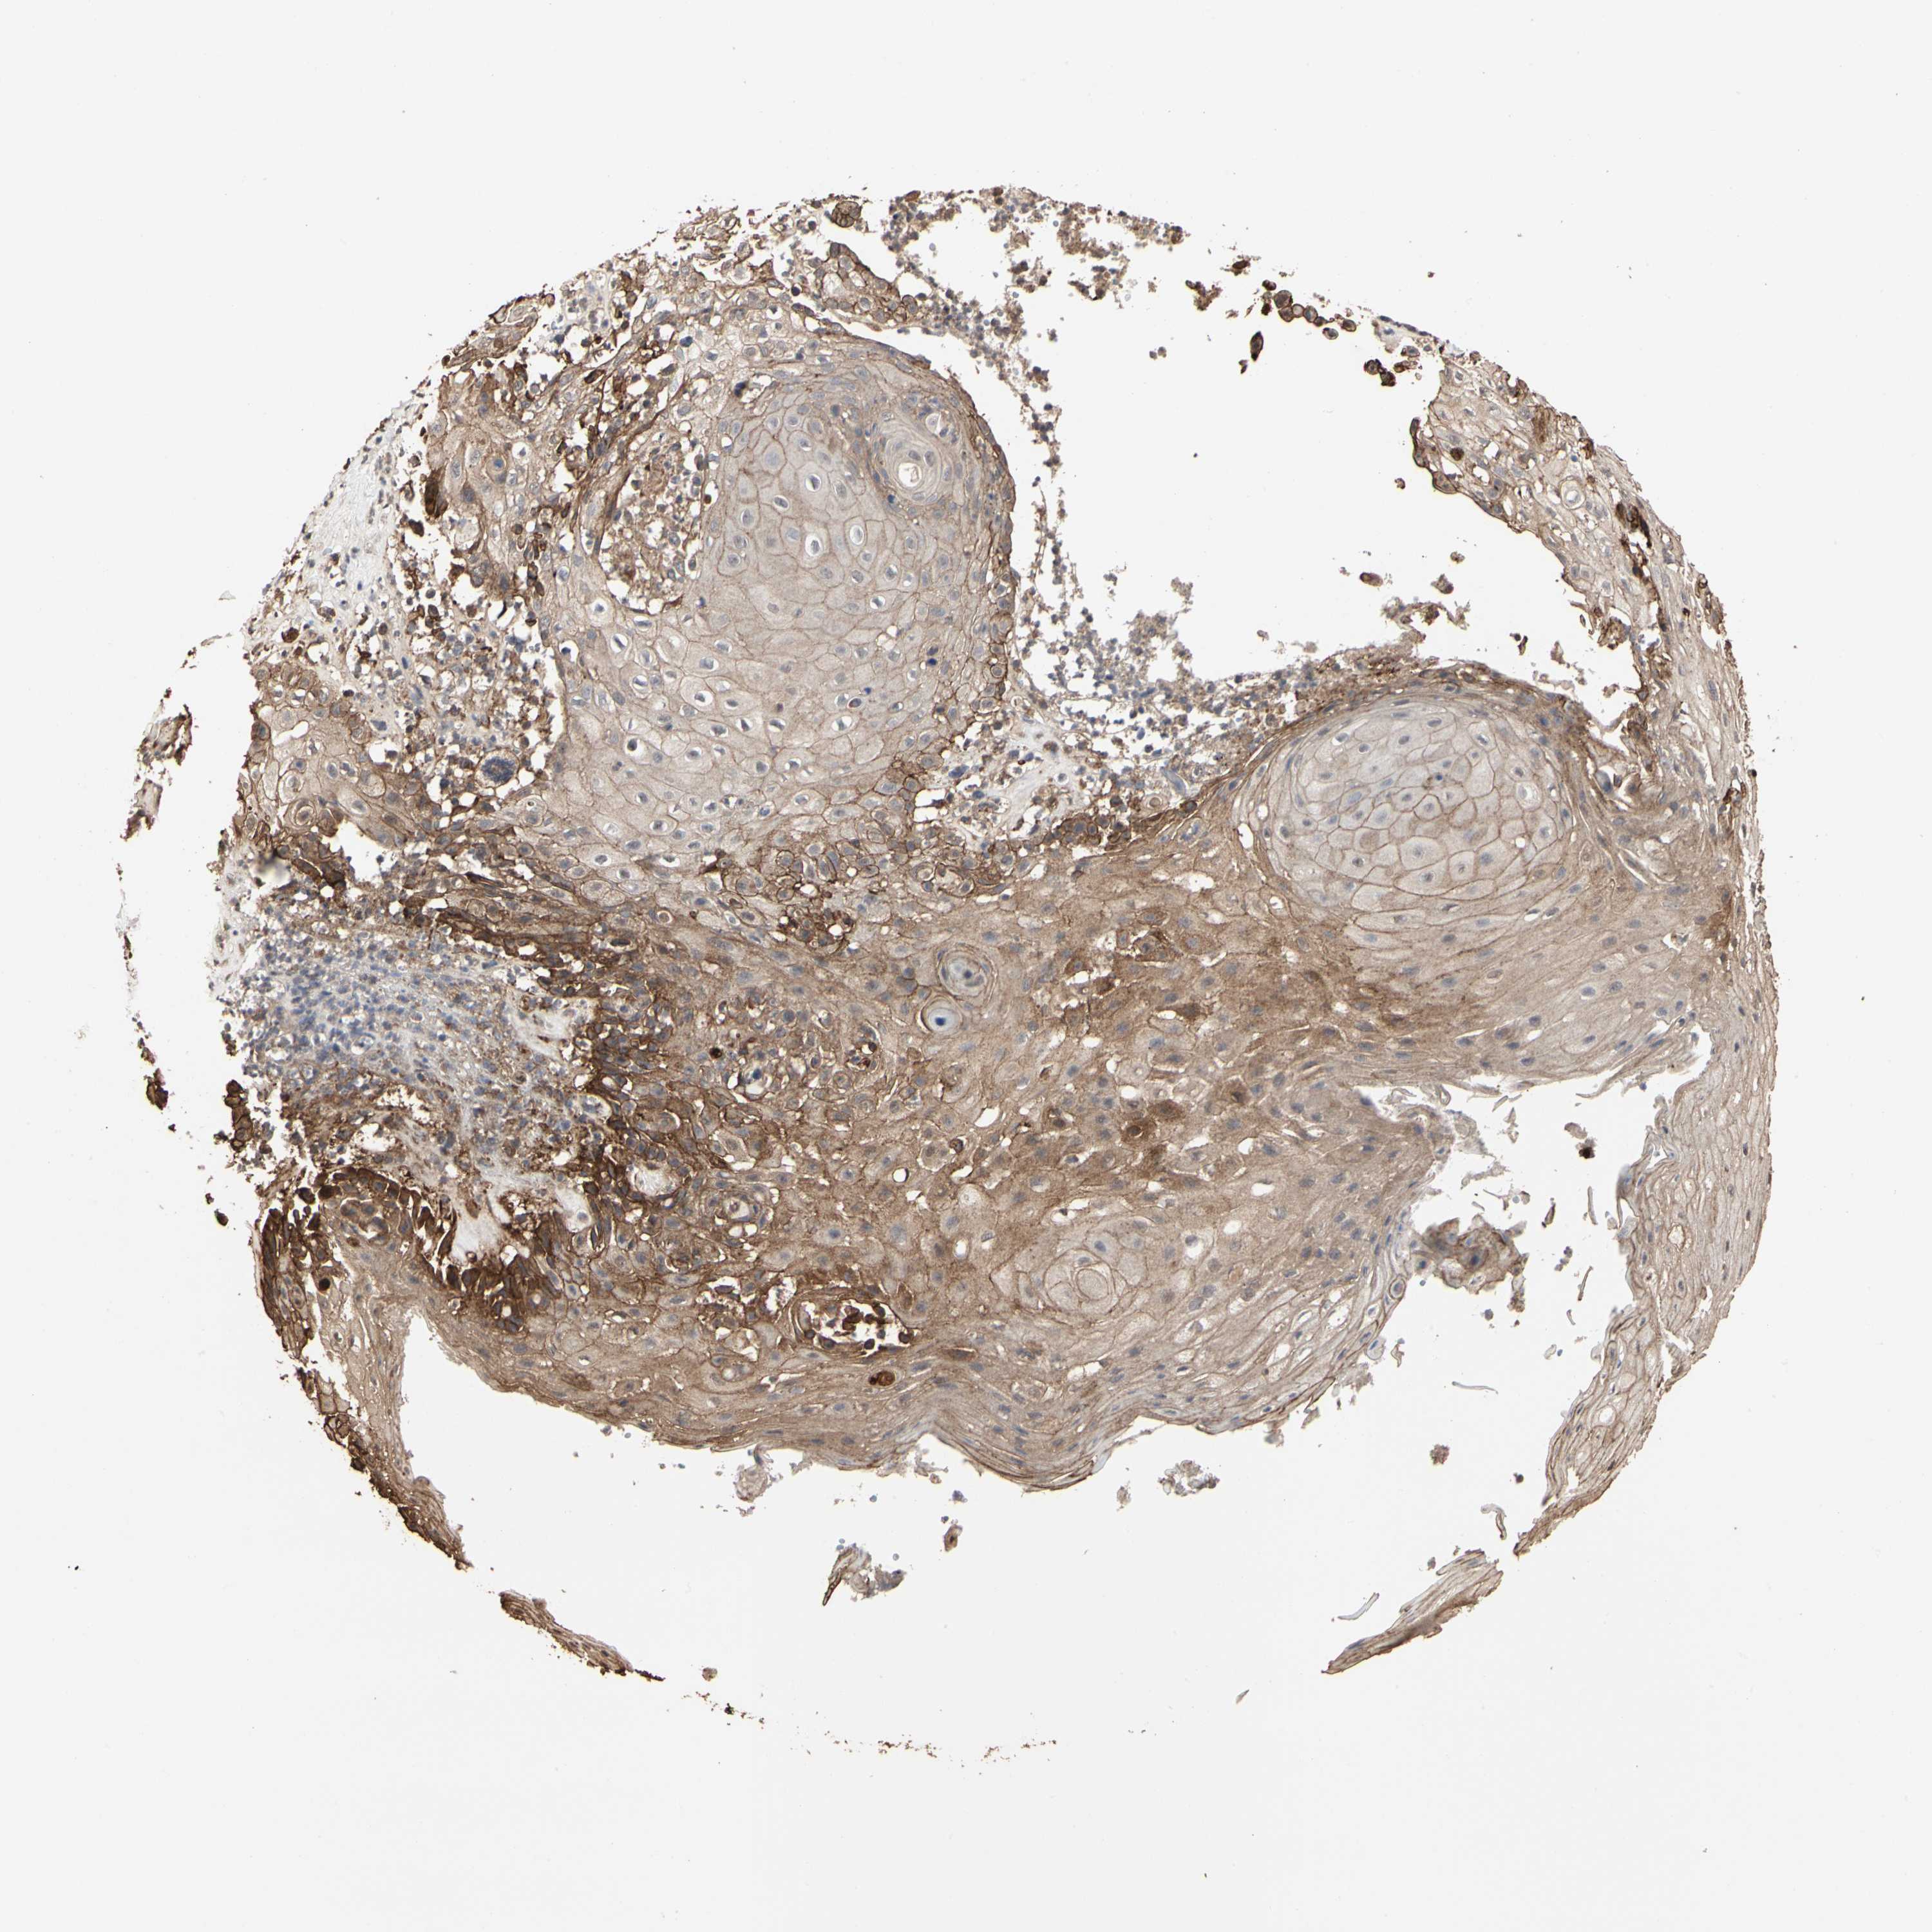

• TAOK1

CANCER SKIN CANCER Show tissue menu

Basal cell and squamous cell cancer

Human cancer

SKIN CANCER - Protein expressioni

A mouse-over function shows sample information and annotation data. Click on an image to view it in a full screen mode. Samples can be filtered based on level of antibody staining by selecting one or several of the following categories: high, medium, low and not detected. The assay and annotation is described here.

Antibody stainingi

Antibody staining in the annotated cell types in the current human tissue is reported as not detected, low, medium, or high, based on conventional immunohistochemistry profiling in selected tissues. This score is based on the combination of the staining intensity and fraction of stained cells.

Each image is clickable and will lead to virtual microscopy that enables deeper exploration of all samples and also displays staining intensity scores, fraction scores and subcellular localization as well as patient and tissue information for each sample.

Antibody HPA007669

Staining

High

Medium

Low

Not detected

Intensity

Strong

Moderate

Weak

Negative

Quantity

>75%

75%-25%

<25%

None

Location

Nuclear

Cytoplasmic/membranous

Cytoplasmic/membranous,nuclear

Squamous cell carcinoma, NOS

Basal cell carcinoma